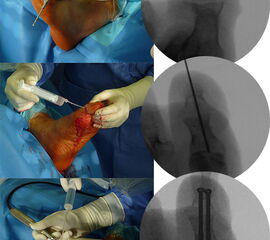

Zur Korrektur der Fehlstellung und zur Ulkus-Behandlung kann in minimalinvasiver Technik über ein mediales Portal eine Walzenfräse in das Interphalangealgelenk eingebracht werden. Über ein zweites laterales Portal wird nach Resektion der Gelenkflächen der Knochenabrieb ausgespült. Sobald ausreichend Knochen reseziert ist, kann die Zehe gestreckt werden. Die beiden abgetragenen Knochenflächen werden im Sinne einer IP-Arthrodese aufeinandergestellt. Es erfolgt dann die Transfixation der Arthrodese mittels ein bis zwei, über die Spitze der Endphalanx eingebrachten Zugschrauben. Problematisch ist es, wenn sich an dieser Stelle unverändert ein Ulkus befindet. In diesem Falle ist die Transfixation der Arthrodese mit zwei perkutan eingebrachten, schräg verlaufenden Kirschner-Drähten weniger risikoreich. Der Eintrittspunkt der K-Drähte befindet sich hier medial und lateral im Bereich der Endphalanx. Bei persistierender Fehlstellung kann je nach Vorspannung eine Tenotomie der EHL- und/oder der FHL-Sehne durchgeführt werden. Normalerweise entspannt sich die Sehne durch die Knochenresektion und den damit verbundenen Längenverlust ausreichend. Zur Korrektur der Fehlstellung „wird die Knochenlänge an die Sehnenlänge angepasst“.

Zum Lesen der Bildbeschreibung und zur Vollansicht bitte die Bilder anklicken.

Abbildung 5

Abbildung 6

Abbildung 7

Abbildung 8